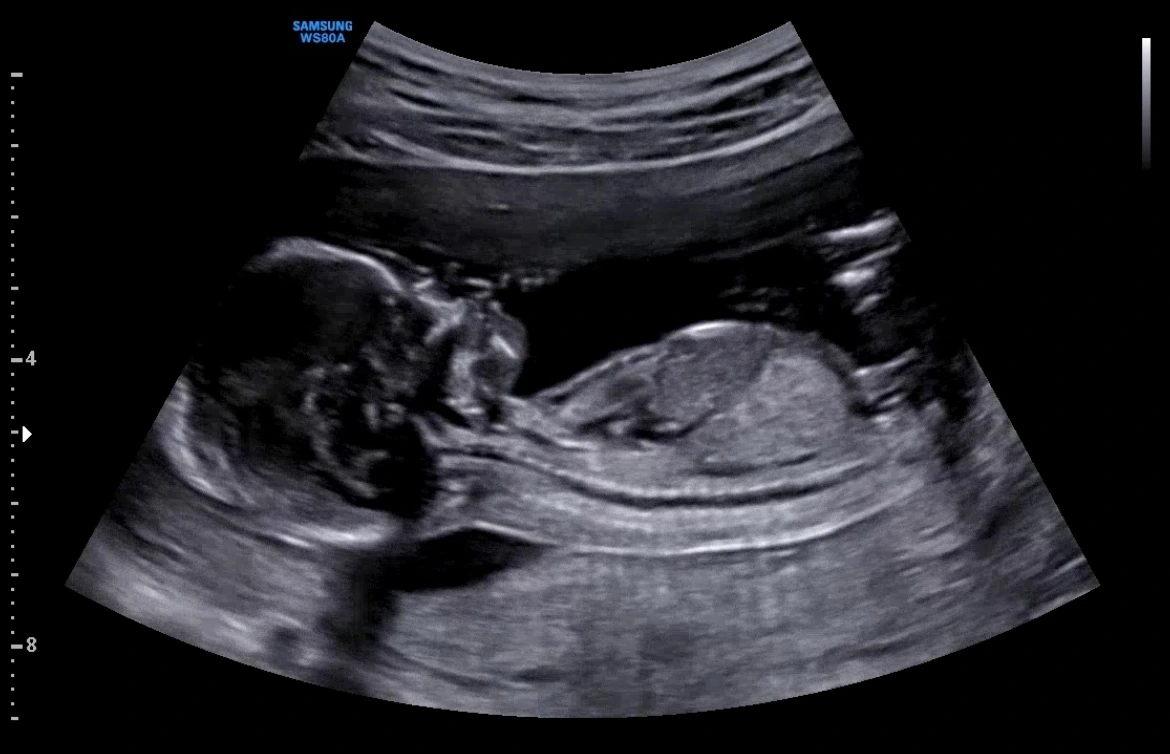

다시 택시를 잡고 원래 다니던 산부인과로 갔다. 접수를 하고 30분을 기다리는 데, 1시간 같았다. 검진을 다녀간 지 얼마 안 되어서, 또 왔냐는 표정이셨지만, 교통사고를 당했다고 말씀드렸다. 초음파로 확인을 했는데, 아가는 괜찮았다.

"뒤에서 박은 경미한 교통사고는, 엄마 양수가 보호해주고 있어서 괜찮아요. 그래도 혹시 모르니 며칠은 경과를 지켜보시고, 피가 너무 많이 나거나 안 좋다 싶으면 꼭 대학병원으로 가세요."

초음파 상에 베짱이는 잘 움직이고 있었다. 심장소리도 괜찮았다. 괜찮다는 말을 한 귀로 들으며, 아가 모습을 보자 숨이 쉬어졌다. 남편에게 괜찮다는 연락을 하고, 학교로 향했다. 내가 안 올 거라고 생각했는지, 동기들도 선생님도 놀란 표정이었다. 얼른 끝내고 집에 가고 싶었다. 최대한 아무렇지 않은 표정으로 발표와 질의응답을 끝냈다. 통과는 할 것 같았다. 동기들끼리 마무리 회식을 한다고 했지만, 그냥 집에 왔다. 침대에 누우니 하얀 천장이 눈에 들어왔다. 남편이 집에 들어올 때까지 움직이지 않고 가만히 배에 손을 올리고 있었다.